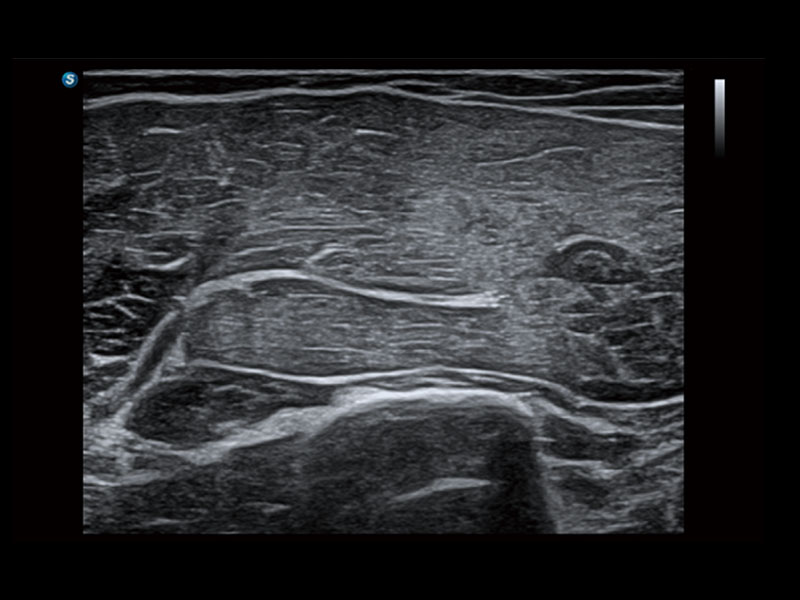

作为开立医疗全新打造的高端床旁笔记本超声,E11不仅具备卓越的图像质量,同时搭载全面高效的自动测量工具,助力医生实现更快速、更精准的床旁诊断。

E11搭载了丰富的自动化测量工具,以及专为POC科室定制的高级功能;同时配备了为急诊医师量身打造的 SonoFast急重症超声流程,以帮助临床医生最大限度的提升工作效率